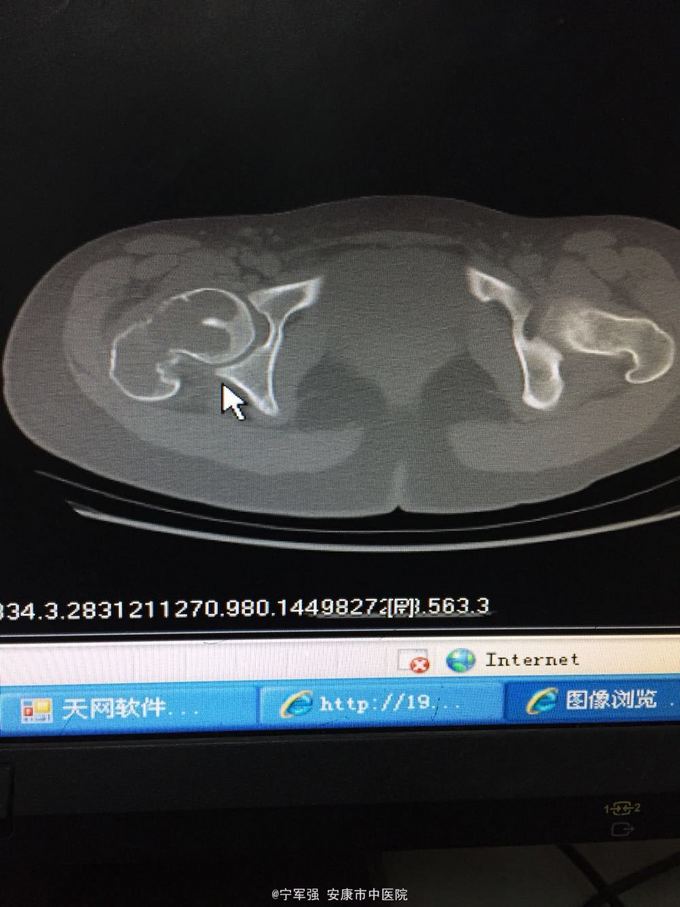

女性,20岁,外伤后右髋部疼痛不适活动受限 伤前身体尚可,5个月前有右大腿不适感,当时未行X线检查

查体:右髋部稍肿,局部压痛(+),纵向叩击痛阳性,右下肢短缩约1.5CM,末梢血运及皮肤感觉良好。 肿瘤标志物(-),碱性磷酸酶不高。

右股骨颈病理性骨折 处理:1.进一步完善检查髋关节MRI。 2.病检,确定性质; 3.消肿对症治疗; 4.择期植骨内固定术